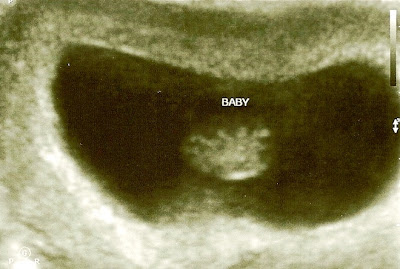

Here is her very first picture! She looks like a little gummy bear here! We also got to hear her heartbeat at this appointment. She was about 7 weeks old here!